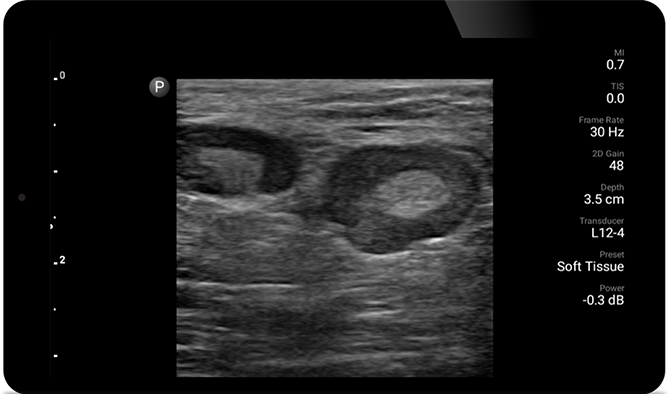

Los exámenes de ultrasonido pueden mejorar su capacidad para identificar y tratar con éxito los abscesos cutáneos.

Ultrasonido POC para tejidos blandos